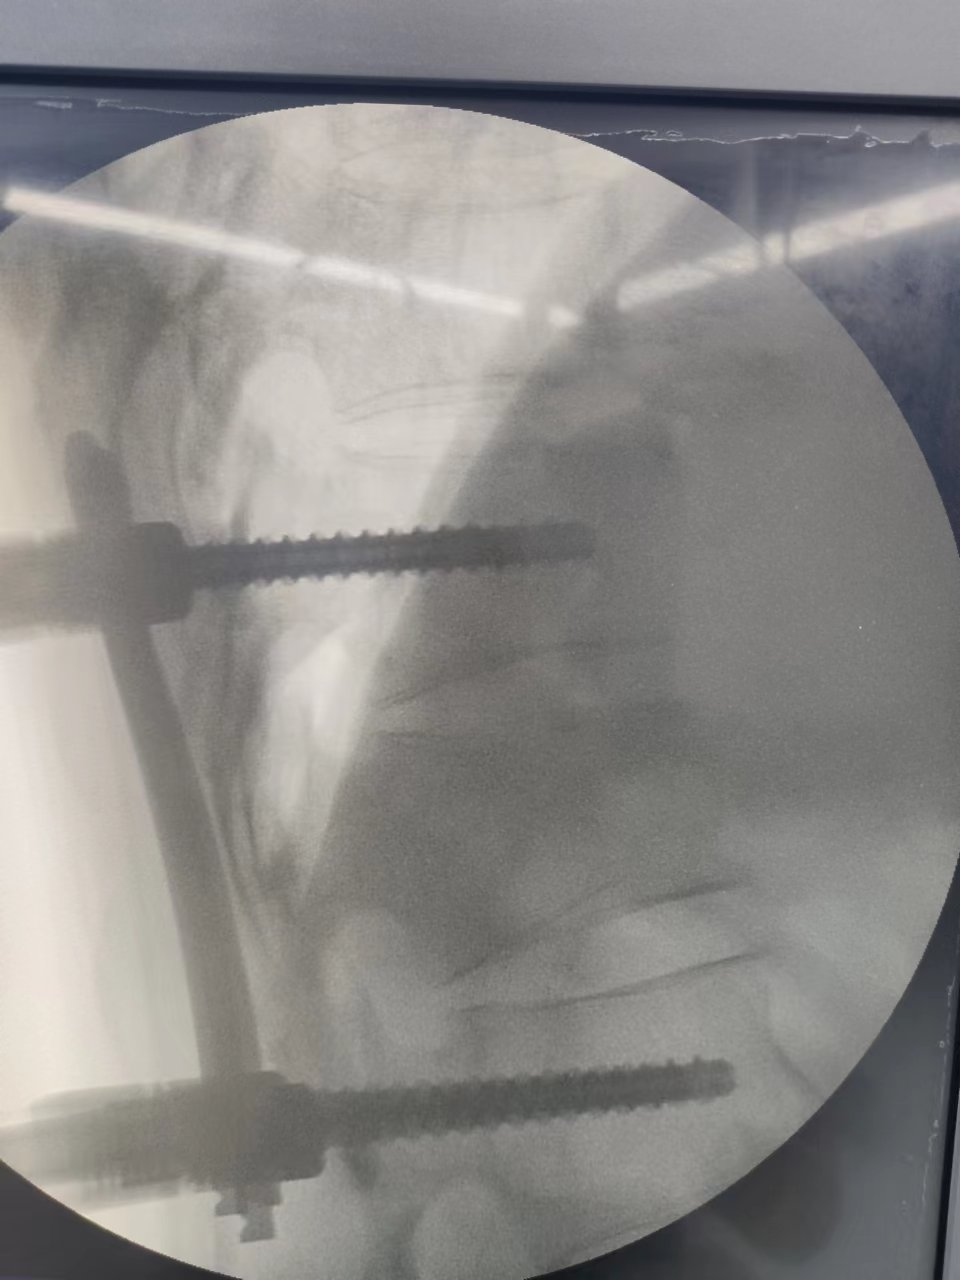

經過充分的術前準備,在麻醉科、手術室等的密切配合,骨科團隊通力合作,手術順利完成,術中4個釘道切口長度僅為1.5cm。

▲透視見椎體高度相高度恢復滿意